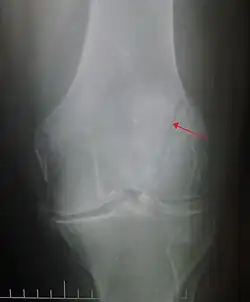

Patella fracture

| A fracture of the patella seen on a lateral view | |

A patella fracture is a break of the kneecap.[1] Symptoms include pain, swelling, and bruising to the front of the knee.[1] A person may also be unable to walk.[1] Complications may include injury to the tibia, femur, or knee ligaments.[2]

It typically results from a hard blow to the front of the knee or falling on the knee.[1]The patella can also be fractured indirectly. For example, a sudden contraction of the quadriceps muscle in the knee can pull apart the patella.[1]Diagnosis is based on symptoms and confirmed with X-rays.[3] In children an MRI may be required.[3]